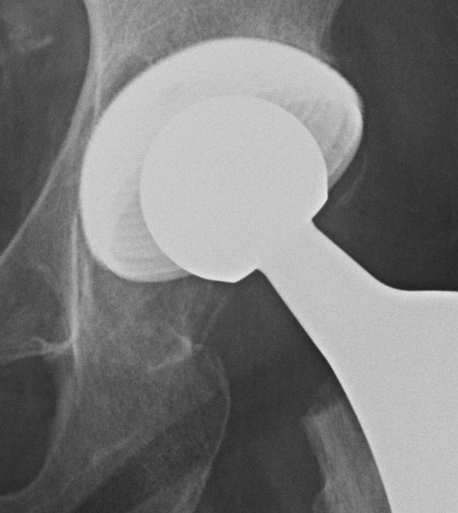

Ceramic on poly THA S&N oxinium on poly S&N ceramic on ceramic